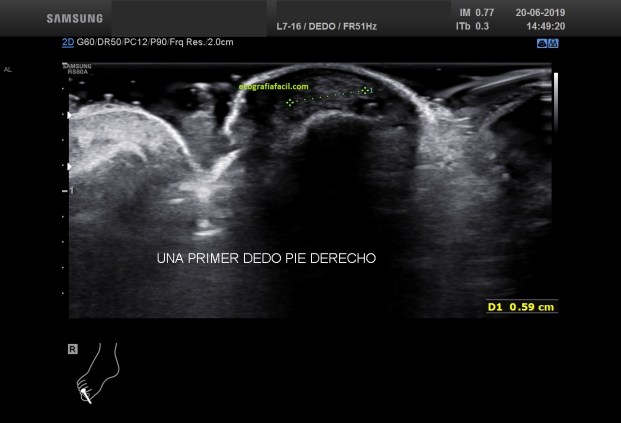

En la imagen del corte sagital de la uña del primer dedo del pie observamos una anatomía muy similar a la de la imagen de referencia de normalidad, con una salvedad, en el espacio subungueal puedes observar una imagen redondeada, hiperecogénica que está señalada con una pequeña flecha roja. Ahora que hemos localizado algo anormal en esa localización, necesitamos estudiarlo y medirlo en dos proyecciones (fig 3 y 4), después ponerle el doppler, color y pulsado (fig 5 y 6). Pon atención a los pictogramas sobre todo en la imágenes con medidas.

In the image of the sagittal cut of the nail of the first toe we observe an anatomy very similar to that of the normality reference image, with a caveat, in the subungual space you can observe a rounded, hyperechogenic image that is indicated with a small Red Arrow. Now that we have located something abnormal in that location, we need to study and measure it in two projections (fig 3 and 4), then put the doppler, color and pulsed (fig 5 and 6). Pay attention to pictograms especially in images with measurements.